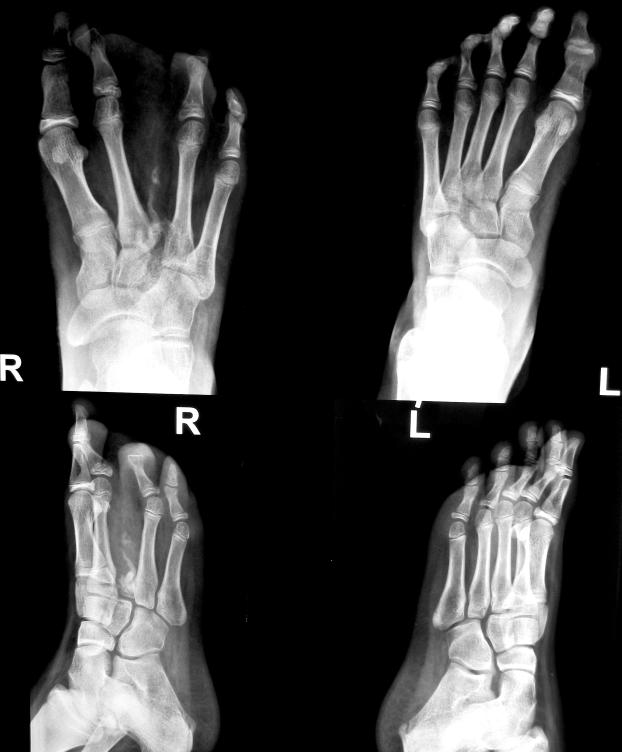

10 YEAR OLD GIRL RIGHT LOWER LIMB INVOLVEMENT RIGHT FOOT IN PARTICULAR

2nd & 3rd toes mainly involved

Splaying of foot

I month post-op

2 YEARS POST-OP

Wears all footwear comfortably, satisfied